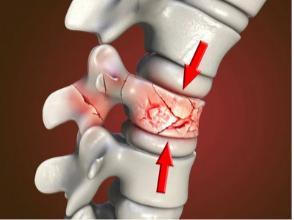

Les tassements vertébraux constituent une pathologie fréquente chez la personne âgée. Ils correspondent à des fractures des corps vertébraux, souvent d'origine ostéoporotique (fragilité osseuse par déminéralisation) et parfois secondaire à une lésion osseuse.

La vertébroplastie ou cimentoplastie est une technique mini-invasive initialement développée dans le milieu des années 1980, qui consiste en l'injection d'un ciment médical dans une vertèbre.

La kyphoplastie est une variante de la cimentoplastie, dont le but est de restaurer la hauteur de la vertèbre en plus de l'injection de ciment.